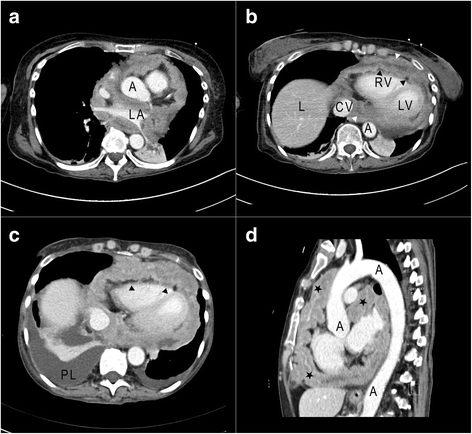

Case presentation: We report a case of a 45-year-old white woman whose pericardial mesothelioma was initially misdiagnosed as pericardial involvement of an autoimmune disease (systemic lupus erythematosus). After several relapses of pericardial effusion, a computed tomography scan and a biopsy with histological analysis were performed revealing neoplastic growth.